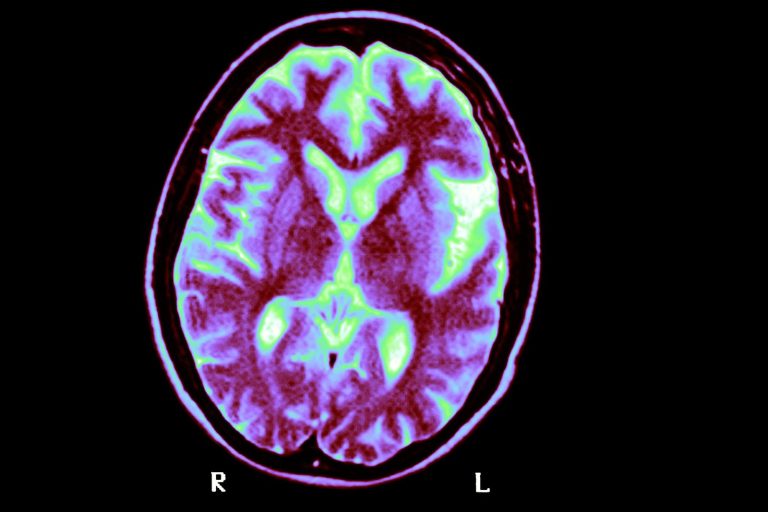

МРТ головного мозга человека с болезнью Альцгеймера. Новое исследование предполагает, что наличие двух копий генетического варианта под названием APOE4 является